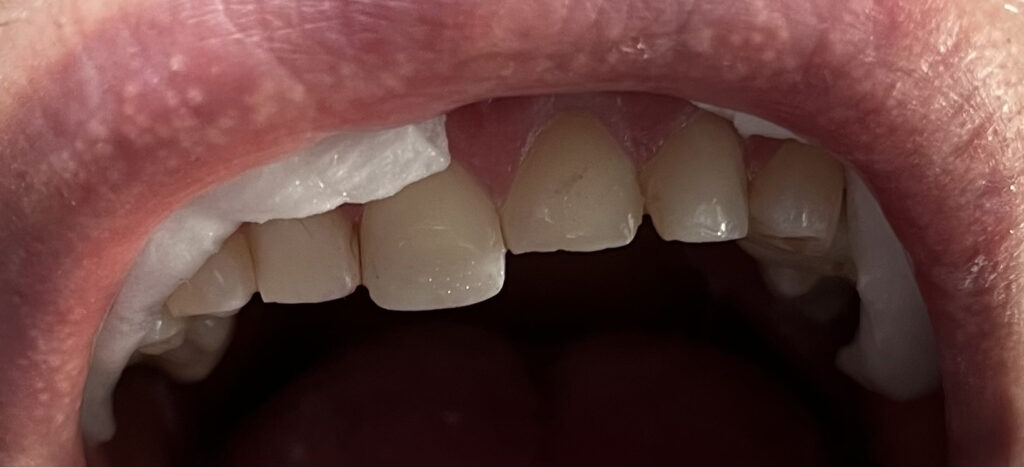

Każdy uśmiech ma swoją historię – my pomagamy ją opowiedzieć na nowo. Dzięki indywidualnie dobranym planom leczenia przywracamy pacjentom nie tylko piękny wygląd zębów, ale również komfort i funkcjonalność w codziennym życiu. Poniżej przedstawiamy wybrane przypadki metamorfoz, które pokazują, jak zaawansowana protetyka, nowoczesne techniki odbudowy oraz precyzyjne leczenie endodontyczne potrafią całkowicie odmienić uśmiech.